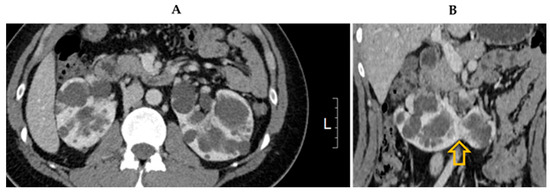

| Age | 24 years |

| Gender | Male |

| Family history | Positive for ADPKD (father and uncle affected) The other five male brothers of the patient’s father were not affected |

| Symptoms | No flank pain No gross hematuria, proteinuria, or albuminuria Hypertension |

| Blood pressure | 150/90 mmHg |

| Physical examination | No palpable abdominal kidney |

| Laboratory examination | Serum creatinine 0.85 mg/dL |

| Estimated GFR 122 mL/min/1.7 m2 Creatinine clearance 104 mL/min Urea clearance 101 mL/min Blood urea nitrogen 16 mg/dL Aspartate aminotransferase 28 U/L Alanine aminotransferase 38 U/L Total bilirubin 0.75 mg/dL Albumin 4.9 g/dL Hb 15.0 g/dL U/A RBC 0-2/HPF, Protein (-), Urine protein-to-creatinine ratio 79 mg/g Urine albumin-to-creatinine ratio 14 mg/g | |

| Kidney volume | Right 542 mL, Left 440 mL |

| Genetic testing | PKD1 mutation (c.165_171del (p.Leu56ArgfsTer15)) |

| Management plan Pedigree | Lifestyle modifications Antihypertensive medications with telmisartan 40 mg Regular monitoring of blood pressure and kidney function every 6 months ![]() |